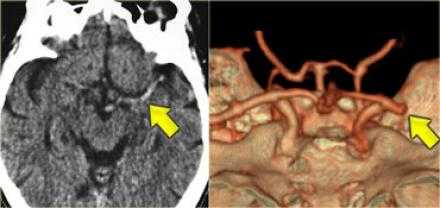

КТА и КТ-перфузия.

После того, как лучевой диагност обнаружил область ишемии, используя КТ-ангиографию ищет тот сосуд, который вовлечён в патологический процесс.

В данном случае признаки инфаркта едва уловимые. Гиподенсная зона в островковой области справа. В данном случае эти изменения соответствуют инфаркту, но у пожилых пациентов с лейкоэнцефалопатией тяжело отдифференцировать эти две разные патологии.

Вышележащие изображения — КТ-ангиография. После выполнения КТА — диагноз инфаркта в области СМА, как на ладоне.

Было проведено исследование для сравнения КТ и МРТ, при котором было установлено, что для выполнения КТ, КТА и КТП при условии, что у вас хорошо сложенная команда, требуется 15 минут. В данном случае была выполнена только КТ так, как выявлено кровоизлияние. В этом случае изначально выполнены КТ без контрастирования и КТ-перфузия так, как выявлен дефект перфузии было целесообразно выполнение КТ-ангиографии, на которой выявлено диссекция левой внутренней артерии.